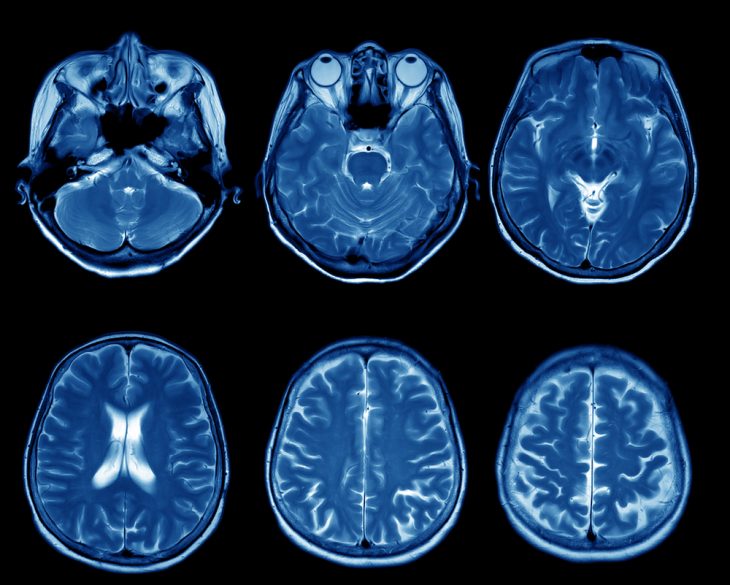

С помощью КТ и МРТ получают чёрно-белые цифровые снимки. Но они существенно отличаются между собой, связано это с принципом действия методов.

В МРТ используется принцип ядерно-магнитного резонанса. Он основан на выявлении магнитного поля вокруг протонов водорода, входящего в состав воды. На снимках более чётко видны мягкие ткани, а вот костные ткани, кальцификаты практически не заметны.

Оба метода достаточно точные, надёжные, позволяющие исследовать структуры головного мозга без хирургического вмешательства, но их эффективность зависит от заболевания.